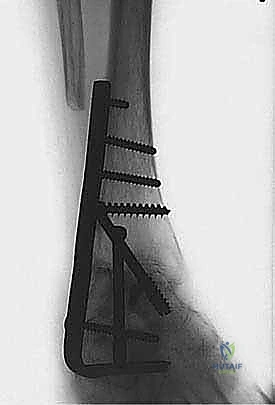

هنا تبرز الصفيحة النصلية (Blade Plate) كالحل الذهبي. تتميز هذه الصفيحة بوجود "نصل" صلب يتم إدخاله بقوة داخل عظمة الكعب، بينما يتم تثبيت الجزء الطولي من الصفيحة على عظمة قصبة الساق بالبراغي. هذا التصميم الهندسي يوفر مقاومة هائلة لقوى الانحناء والدوران، مما يضمن ثباتاً فورياً يسمح للعظام بالالتحام بشكل مثالي.

5. إدخال وتثبيت الصفيحة النصلية (Blade Plate)

هنا تكمن المهارة الجراحية الفائقة. يتم تشكيل مجرى دقيق داخل عظمة الكعب باستخدام إزميل خاص، ثم يتم طرق "نصل" الصفيحة المعدنية بحذر شديد داخل عظمة الكعب لضمان أقصى درجات الثبات.

6. التثبيت النهائي بالبراغي (Screw Fixation)

بعد التأكد من الموضع المثالي للصفيحة والنصل، يتم تثبيت الجزء العلوي من الصفيحة على عظمة قصبة الساق باستخدام براغي قشرية (Cortical Screws) قوية. يتم وضع العظام تحت ضغط ميكانيكي (Compression) لتحفيز الخلايا العظمية على الالتحام السريع.